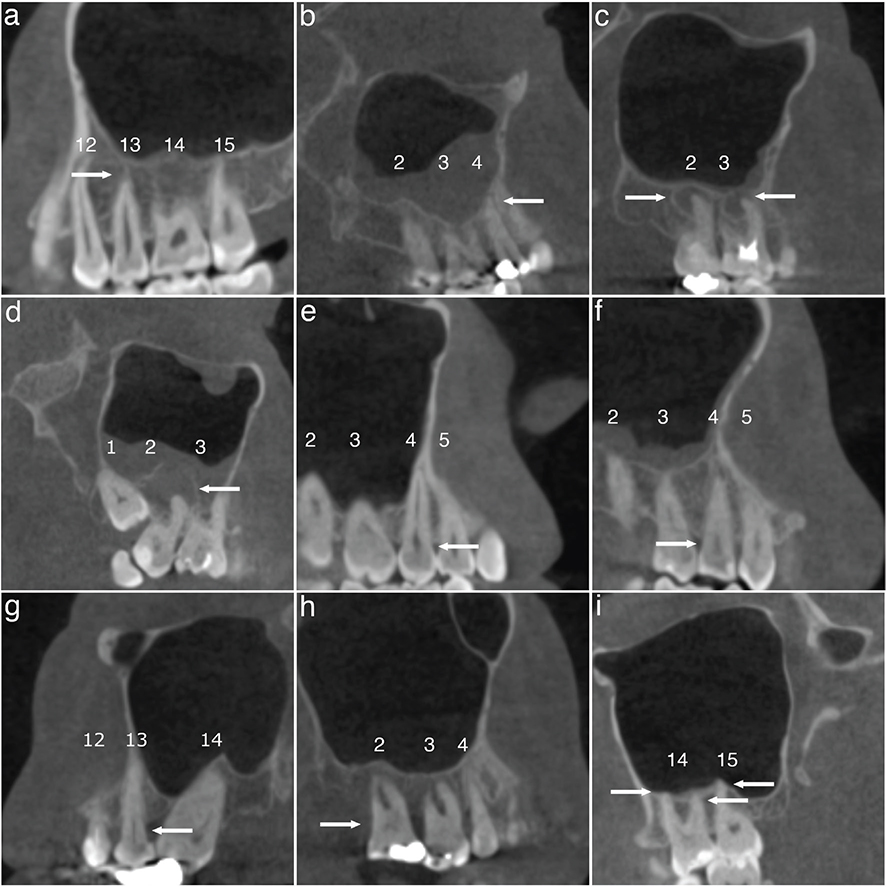

Periapical lesions were classified in four categories (modified from Orstavik et al. [24]): 0 = normal; 1 = widening of the radiolucent periodontal ligament space and minor changes of radiopaque lamina dura; 2 = periodontitis with well-defined and corticated radiolucent area; and 3 = severe periodontitis with exacerbating structures (i.e. large diffuse area of bone destruction in the apical surrounding bone) (Figure 1a–d). Later, categories 0–1 and 2–3 were combined.

Figure 1. Representative CBCT scans of dental findings. Categories of periapical lesions: (a) normal; (b) widening of the radiolucent periodontal ligament space and minor changes of radiopaque lamina dura; (c) periodontitis with well-defined and corticated radiolucent area; (d) severe periodontitis with exacerbating structures. Categories of periodontal bone loss; (e) normal (2 mm or less); (f) mild (2.1 – 3 mm); (g) moderate (3.1 – 5 mm); (h) severe (more than 5 mm). (i) At least one of the tooth roots in contact with the maxillary sinus floor. Teeth are numbered according to World Dental Federation notation (FDI) and each category/finding is indicated by arrows.

Marginal PBL was categorised as follows (modified from Goller-Bulut et al. [7]): 0 = normal (2 mm or less); 1 = mild (2.1 – 3 mm); 2 = moderate (3.1 – 5 mm); and 3 = severe (more than 5 mm). Later, classes 0–1 and 2–3 were combined (Figure 1e–h)

The relationship of teeth with the maxillary sinus was recorded as no contact or at least one of the tooth roots in contact with the maxillary sinus floor (Figure 1i).